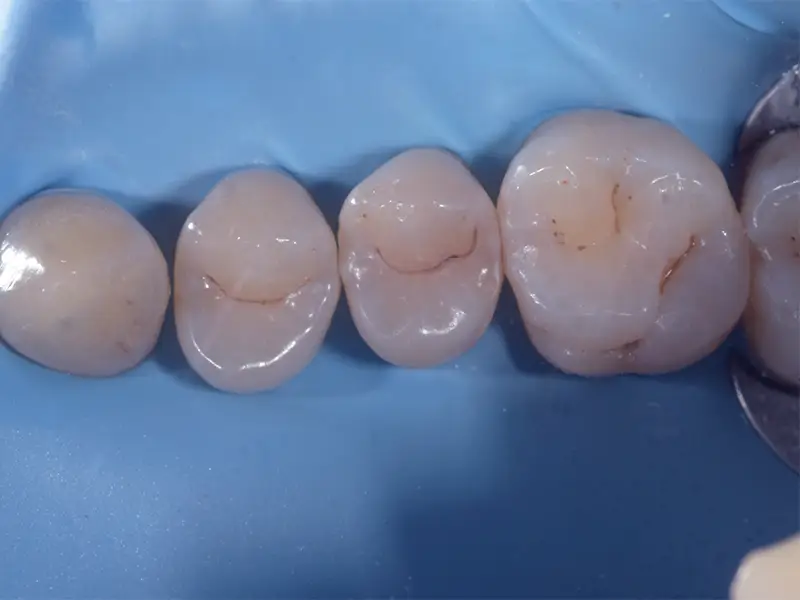

Dopo la diagnosi e la rimozione del tessuto danneggiato, il dente viene ricostruito con materiali compositi estetici di ultima generazione. Utilizziamo la diga di gomma per isolare il campo operatorio e garantire una sigillatura ottimale.

Le ricostruzioni possono essere:

Dirette

- Utilizzo della diga di gomma per sicurezza e precisione